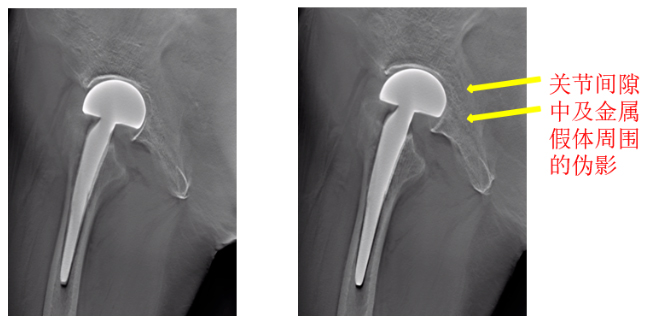

特点1——显著降低重建图像中的金属伪影

特点2——提高金属植入物周围结构的显示能力